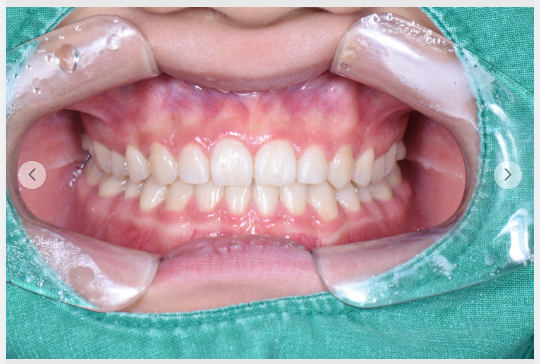

2025년 8월 21일,

마지막 진료 후 환자분은 이렇게 말씀하셨습니다.

"아직 완전히 끝난 건 아니지만... 그래도 이제 웃는 게 덜 어색해요."

환자분의 표정은 이전과 달라졌습니다.

조심스러움은 여전했지만, 그 안에 조금의 여유가 생겼습니다.

비포 앤 애프터 사진을 나란히 놓고 보니, 변화는 명확했습니다.

위아래 치아의 물림이 개선되었고, 얼굴의 좌우 균형이 잡히기 시작했으니까요.